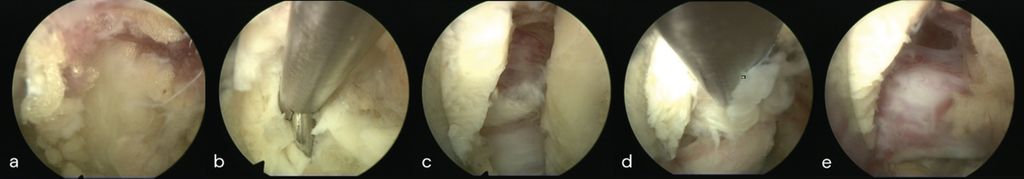

Lumbale vollendoskopische Diskektomie

Die Benefits erzielt die endoskopische Technik bei gering invasiven und technisch niedrig komplexen Eingriffen der Lendenwirbelsäule. Die interlaminäre (IL) und die transforaminäre (TF) endoskopische Diskektomie sind in Bezug auf radikuläre Schmerzreduktion und das funktionelle Outcome der offenen Mikrodiskektomie gleichwertig und hocheffektiv. Ruetten et al. konnten eine signifikant geringere Rate postoperativer Lumbago-Symptomatik nachweisen. Vorteile ergeben sich durch kürzere Operationszeiten, reduzierten Blutverlust, niedrigere Komplikations- und Revisionsraten sowie einen geringeren postoperativen Analgetikabedarf.16In einer prospektiven randomisierten Studie an 143 Patienten zeigten sich im FE-Arm im 2-Jahres-Follow-up ein kürzerer stationärer Aufenthalt und eine deutliche Reduktion radikulärer Schmerzen im Vergleich zur offenen Mikrodiskektomie. Eigene Daten bestätigen diese Ergebnisse mit einer 90-Tage-Wiederaufnahmerate von lediglich 2% und einer mittleren Aufenthaltsdauer von 2,6 Tagen.17 Die Rezidivrate hängt sowohl von patientenbezogenen als auch von technischen Faktoren ab.18 Im direkten Vergleich ist die endoskopische Diskektomie der offenen Technik hier nicht unterlegen. Abbildung 4 zeigt die endoskopische Sicht einer interlaminären Diskektomie L5/S1 rechts (a–e) mit Darstellung des Sequesters (c, d) und der dekomprimierten Nervenwurzel S1 (e).